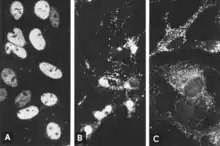

Acute infection of postnatal pigs, including pregnant dams that subsequently develop reproductive failure, is usually subclinical.[11][12][13][14][15][16] However, in young pigs and probably in older breeding stock as well, the virus replicates extensively and is found in many tissues and organs with a high mitotic index. Viral antigen is especially concentrated in lymphoid tissues[13][14] (Fig. 3A, B). Many pigs, irrespective of age or sex, have a transient, usually mild, leukopenia sometime within 10 days after initial exposure to the virus.[11][17][15][16] PPV and other structurally similar viruses have been identified in the feces of pigs with diarrhea.[18][19] However, there is no experimental evidence to suggest that PPV either replicates extensively in the intestinal crypt epithelium or causes enteric disease as do parvoviruses of several other species.[13][20] PPV also has been isolated from pigs with lesions described as vesiclelike. The causal role of PPV in such lesions has not been clearly defined.[21]

Several investigators have used IF microscopy to follow the development of PPV in cell culture.[31][40][60][61][62] In general, the sequence of events is as follows. Viral antigen is detected in the cytoplasm of cells soon after infection if the inoculum contains a high titer of virus and viral antigen. Most, if not all, of this early cytoplasmic fluorescence is the result of antigen phagocytized from the inoculum.[60][63] By sequential examinations, such antigen can be demonstrated first on the external surface of the cytoplasmic membrane and later within the cytoplasm, often relatively concentrated in a juxtanuclear location. The first unequivocal evidence of viral replication is the appearance of nascent viral antigen in the nucleus (Fig. 2A). In at least some infected cells, nascent antigen next appears in the cytoplasm in sufficient quantity that both cytoplasm and nucleus are brightly fluorescent. Infected cells commonly seen in the lung of fetuses that develop a high titer of antibody for PPV probably represent this stage of replication (see Fig. 8C). Affected cells subsequently round up, become pyknotic, and disintegrate with release of virus and viral antigen (Fig. 2B). Other cells in the culture that are not at the appropriate stage to support viral replication continue to phagocytize and accumulate viral antigen in their cytoplasm (Fig. 2C). A second wave of viral replication can be induced if these cells are stimulated to enter the S phase of the cell cycle as, for example, by the addition of fresh culture medium.

Identification of viral antigen by IF microscopy is a reliable and sensitive diagnostic procedure. Sections of fetal tissues are prepared with a cryostat microtome and are then reacted with standardized reagents.[5][26] The test can be completed within a few hours. In the absence of a fetal antibody response, antigen is seen throughout fetal tissues (Fig. 8A, B); even when antibody is present, infected cells usually can be detected in fetal lung (Fig. 8C).